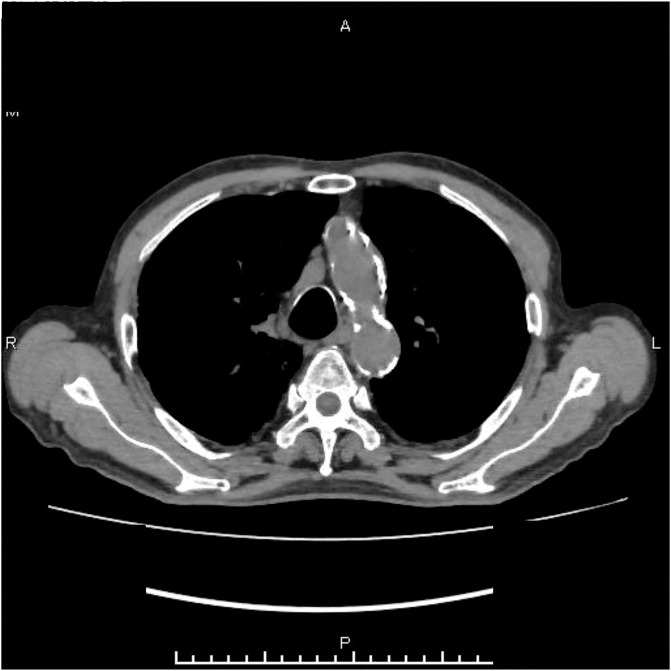

Diffusion-weighted whole-body imaging with background body signal suppression has been used to diagnose fever of unknown origin. An 86-year-old man who underwent bile duct jejunostomy for bile duct cancer presented with fever (body temperature, 40°C). Escherichia coli was detected in blood cultures. Diffusion-weighted whole-body imaging with background body signal suppression revealed accumulation in the aortic arch. Therefore, infectious aortitis secondary to retrograde cholangitis was diagnosed. The patient was treated with antibiotics, and the aortic arch accumulation disappeared. Diffusion-weighted whole-body imaging with background body signal suppression is a useful modality for diagnosing vasculitis and assessing treatment effectiveness.